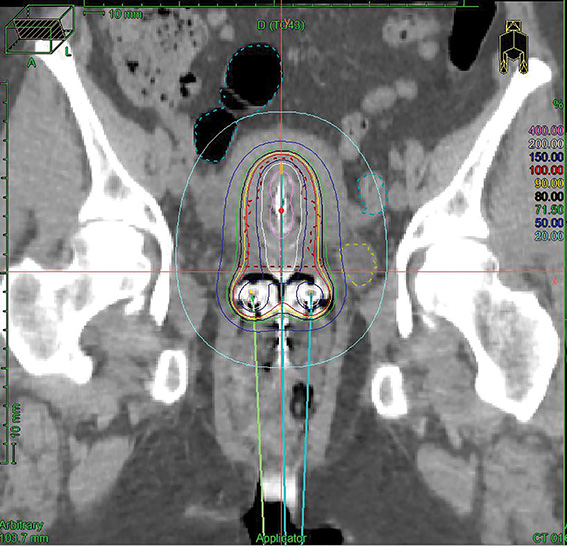

Genesis Cancer Care is the only WA clinic to use the ground-breaking brachytherapy to treat cervix cancer, where an applicator inserted into the uterus delivers a high burst of concentrated radiation.

“Lots of studies have shown that if you combine the external radiotherapy with the brachy treatment, there is a higher survival rate,” says Dr Sia.

“It’s a very effective complementary treatment.”